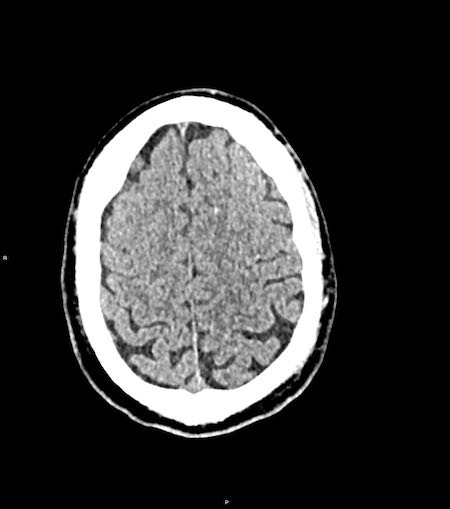

Tụ máu dưới màng cứng đồng tỷ trọng

Khi tụ máu dưới màng cứng tiến triển theo thời gian, tỷ trọng của khối tụ máu sẽ giảm dần và có thể tương đương với tỷ trọng của nhu mô não, khiến việc phát hiện tổn thương trở nên khó khăn.

Đây là trường hợp tụ máu dưới màng cứng đồng tỷ trọng rất khó phát hiện (các mũi tên).

Lưu ý rằng ở mức cắt cao hơn có tụ máu dưới màng cứng hai bên.